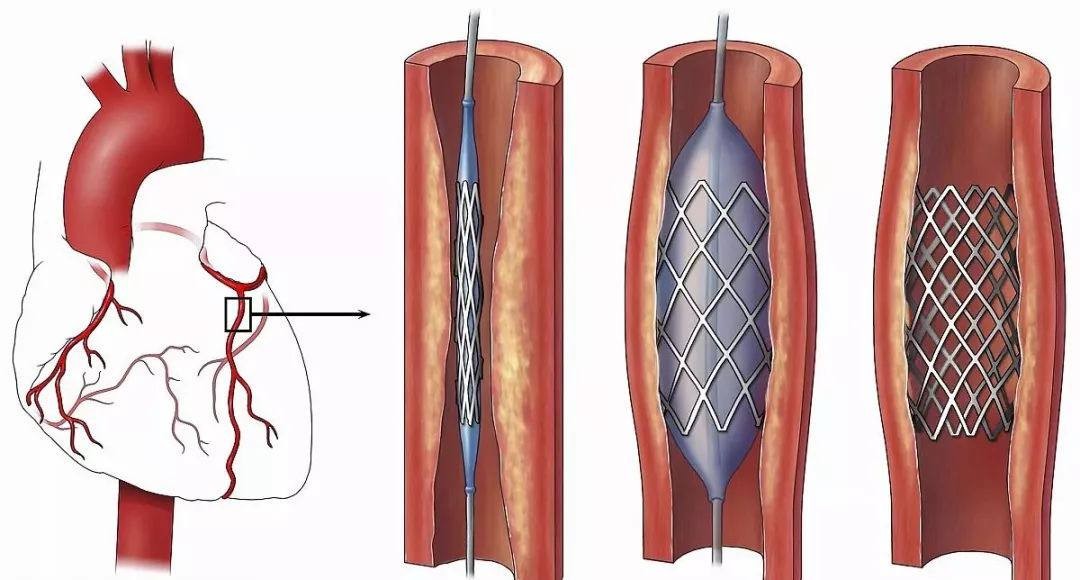

外周静脉取栓支架

项目类型

器械质押区

起投金额

200USDT

每日释放:1

释放周期:97 天

已购: 150000

剩余: 0